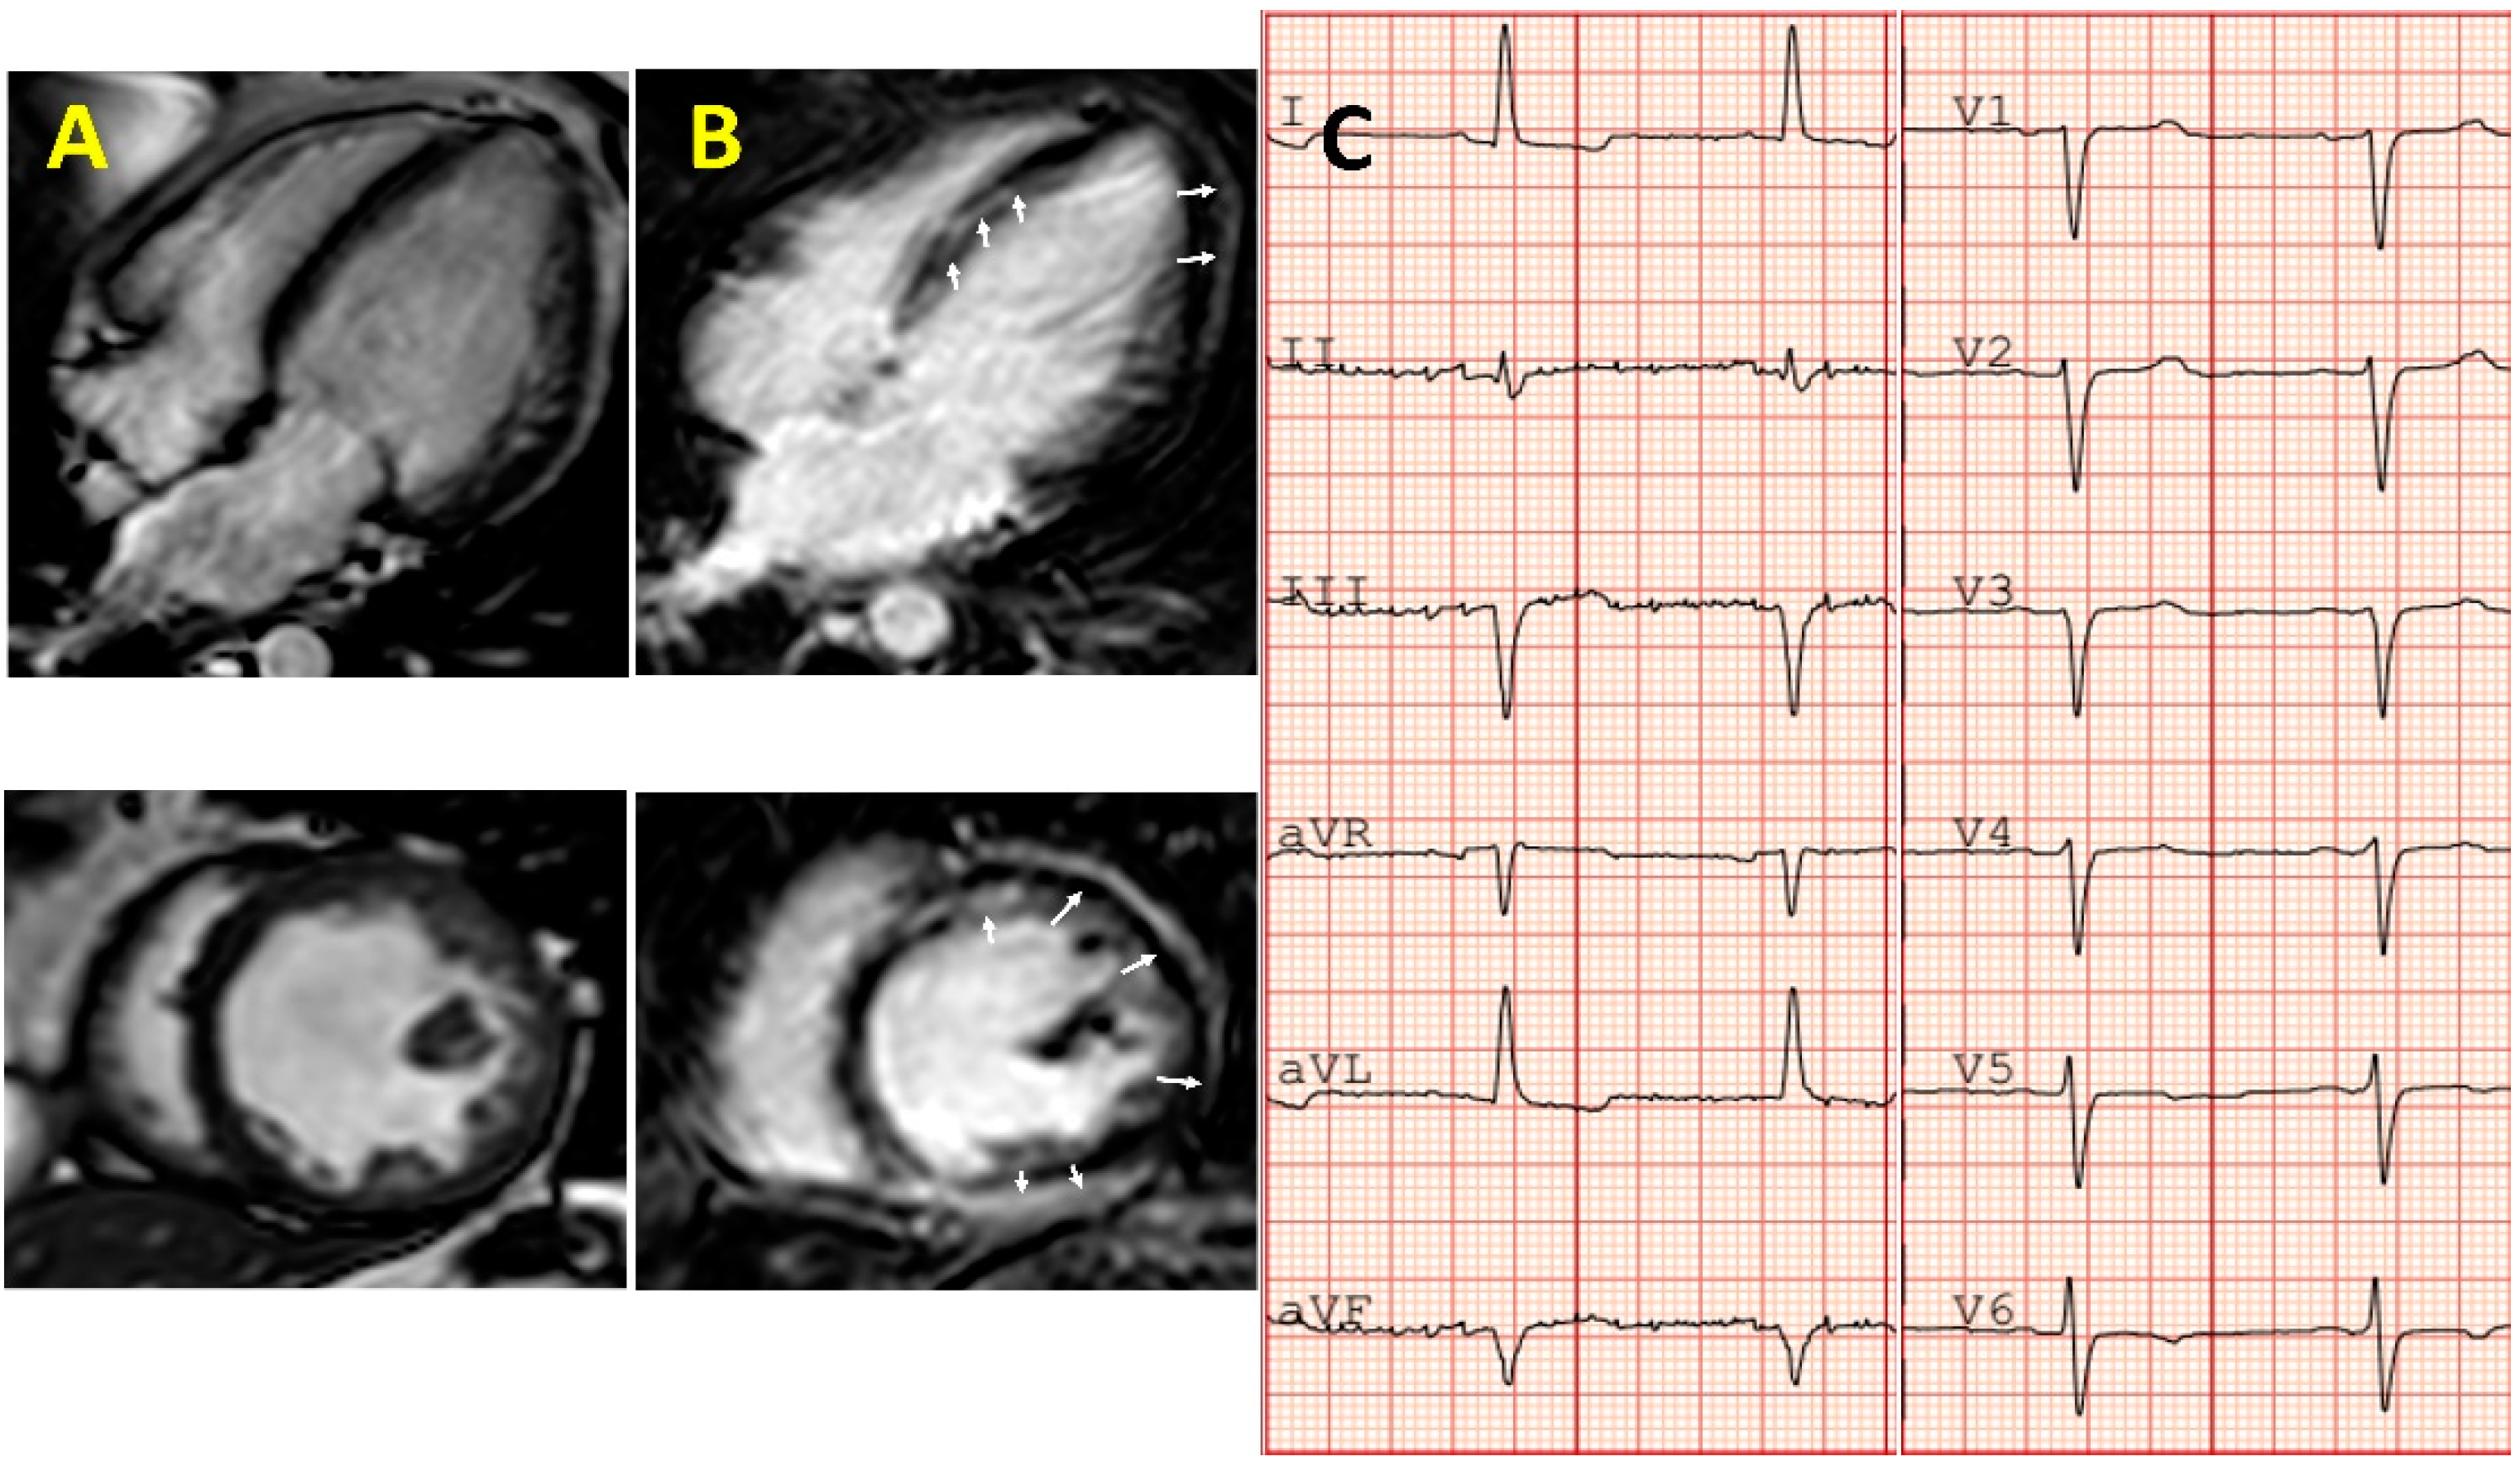

ACM is a disease characterized by the loss of myocardial tissue and subsequent fibro-fatty replacement [32]. Initial description of the disease supported the hypothesis of a right ventricle (RV) condition. LV involvement was then described as the disease progressed, and lately, typical primary LV forms have been recognized [32,33]. When LV function is preserved, the cardiac output is maintained and predominant symptoms are secondary to life threatening ventricular arrhythmia. Diagnosis of left forms of ACM are characterized by “atypical DCM” features such as early onset of arrhythmia despite mild-moderate degrees of systolic impairment and myocarditis-like pattern of late gadolinium enhancement (LGE) on cardiac magnetic resonance (CMR) (Figure 2). ACM is the most inflammatory idiopathic cardiomyopathy that can develop in the crisis of myocarditis [32,34].

The left form of ACM can also present like DCM (in early phases as hypokinetic non-dilated form). The arrhythmic burden in ACM compared to DCM is higher. Accurate diagnosis of a prior ACM is important not only because of the likely impact of the myocardial toxicity of chemotherapy, but also because of the life threatening arrhythmias that can precede the development of severe systolic impairment [32]. A high suspicion of ACM should be taken when there is a CMY, history of ventricular arrhythmia, and family history of sudden death. Of note, the pattern of LGE on CMR is typically very similar to that of myocarditis and cardiotoxicity from chemotherapy (Table 1 and Figure 2). In the absence of a baseline CMR, evaluation of cardiotoxicity after chemotherapy can be difficult. Patients with a personal or familiar diagnosis of CMY undergoing chemotherapy should have a full cardiac evaluation including a baseline CMR. An illustrative case of a young woman with CCM in whom following familial evaluation was subsequently diagnosed with ACM caused by a DSP p.Q447* is presented in Figure 3.

Additionally, rare variants in genes related to familial CMY have been identified in sporadic individuals and a small case series of patients with CCM [27,86,87,88,89]. The current evidence is based on clinical cases like a woman with epirubicin-induced CMY who was found to be the carrier of the mutation in a sarcomeric gene (MYH7) often associated with HCM or DCM phenotypes [87]. MYH7 variants were also identified by other authors in patients developing severe CCM [86,89]. Some of the common denominators in the clinical features of those cases were an unusual severity of the systolic impairment, unexpectedly soon after therapy and young age. CMR features in patients with genetic variants in HCM associated genes can be a particular pattern of LGE on CMR (Figure 2). A familial form of CCM was suggested in the description of the families in an interesting publication from Wasielewski et al. [89].